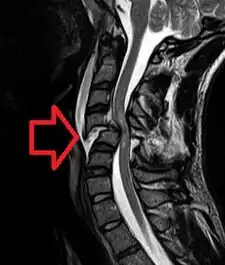

![]() Obrázek magnetické rezonance poranění míchy v krční oblasti | |

K vyšetření a nalezení postižené lokace se užívá nejčastěji rentgenu, pro složitější případy pak také CT a MRI.